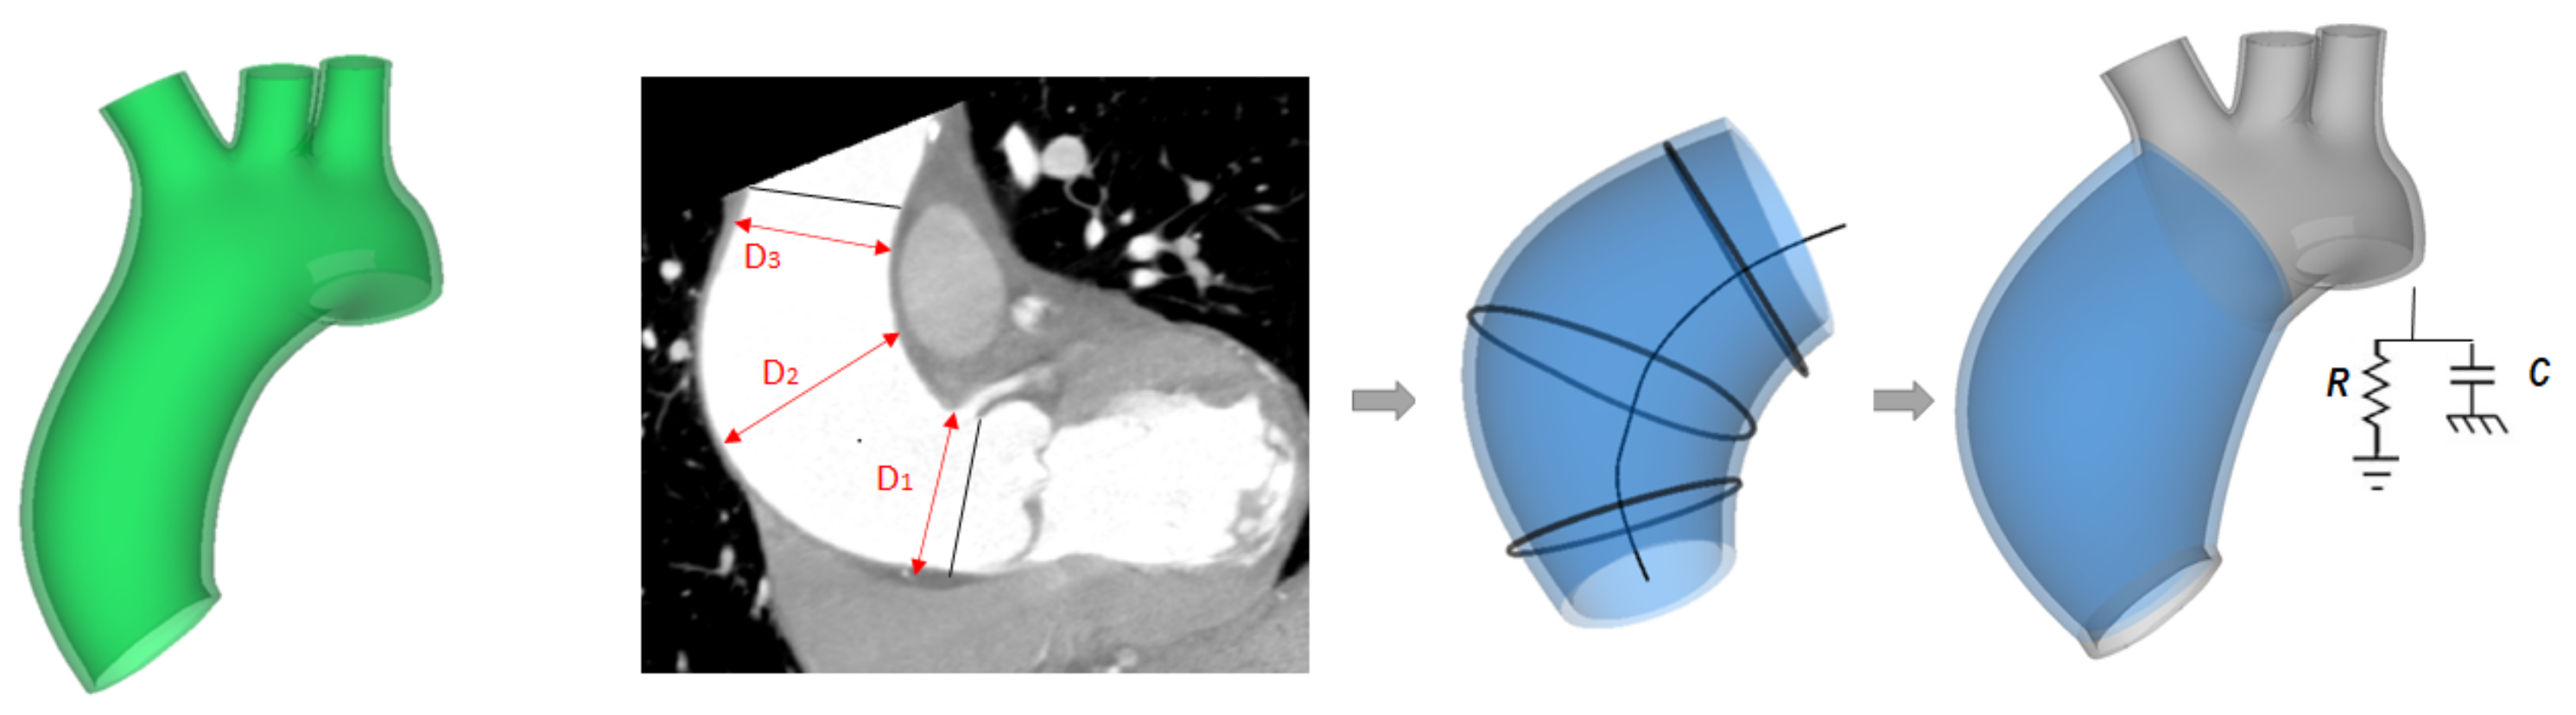

The proposed computational workflow to include the ATAA in the LHHM consisted of three steps: (1) integration of the patient-specific ascending aneurysm anatomy (see Figure 1), (2) assessment of constitutive material descriptors from biaxial testing, and (3) adaptation of the lumped-parameter model of systemic circulation using clinical data collected during patient workup (see Figure 1).

Figure 1.

Workflow showing the modification of the original LHHM to account for the ATAA; the green model (left) shows the original aortic model; measurements of ATAA diameter from CT images (middle-left); ATAA model showing the centerline and curve used for the loft protrusion surface (middle-right); ATAA model showing the coupling with the lumped-parameter model as boundary condition (right).